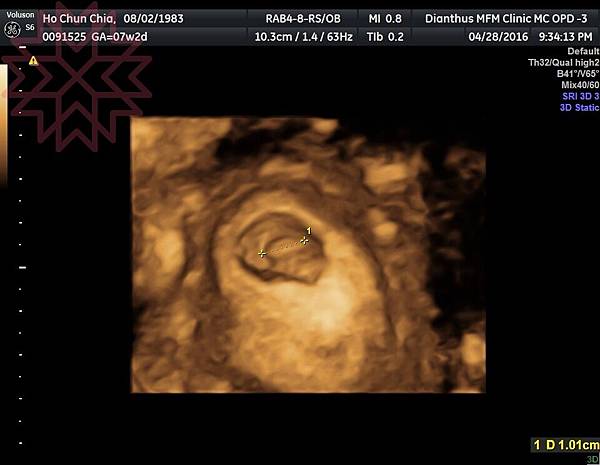

一開始不知道該開心還難過, 但看奇妙的小豆豆, 一點一點長大, 真的很奇妙